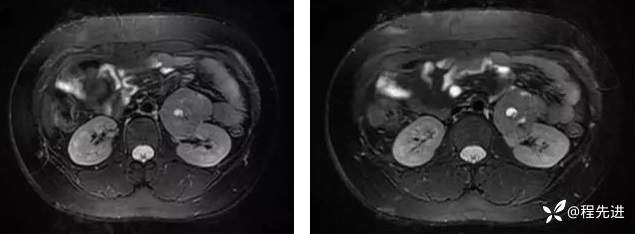

MR平扫+增强:

T2: